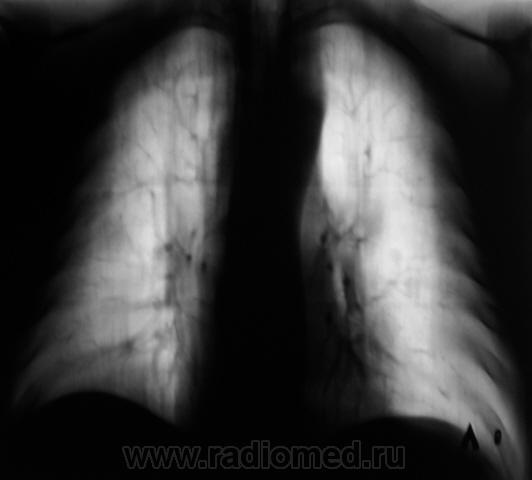

Пациент "взят на контроль" при расшифровке цифровых флюорограмм, дообследован - рентгенография в стандартных проекциях. Ваше мнение коллеги?

Произведены томограммы.